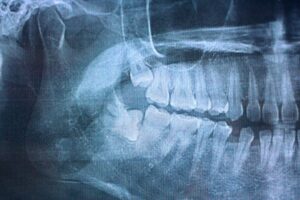

Wisdom tooth removal is one of the most common dental procedures adults undergo, and for most people, recovery goes smoothly. But knowing what to watch for in the days after your extraction can make the difference between a quick recovery and an avoidable complication.

Dry socket is the most common complication following wisdom tooth removal. It occurs when the blood clot at the extraction site is dislodged or fails to form properly, leaving the bone and nerves underneath exposed.